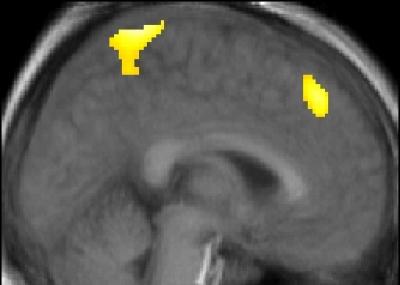

Players were able to learn from their own successful selections but those of their competitor failed completely to increase their neural activity. Instead, it was their competitor's unexpected failures that generated this additional brain activity. Such failures generated both reward signals in the brains of the players, and learning signals in regions involved with inhibiting response. This suggests that we benefit from our competitors' failures by learning to inhibit the actions that lead to them.

Surprisingly, when players were observing their competitor make selections, the players' brains were activated as if they were performing these actions themselves. Such 'mirror neuron' activities occur when we observe the actions of other humans but here the players knew their opponent was just a computer and no animated graphics were used. Previously, it has been suggested that the mirror neuron system supports a type of unconscious mind-reading that helps us, for example, judge others' intentions.